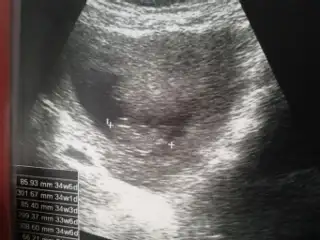

PrenssCvp için teşekkürler . Bide bu son fıtosu var ikiside çok farklı sznkiEki Görüntüle 1363266

On haftalık demişsin çok erken. Bu hafta kız erkek pek fark olmazki güzelim. Erkek geçti ama içimden erkege benzettim yani. Gönlüne göre olsun inşallahLütfen bi bakın çok merak ediyorum

Ben zaten çok anlamam tatlım Allah gönlüne göre versin inşallah. Ben de 18 haftada öğrenmiştim iki hafta daha merak et bakalim sonra net öğrenirsin. Beklemesi merak etmesi bile çok güzellSağol Cnm inş.. Radyoloji uzmanim bakmıştı bu ggörüntüler onun baktıkları içindendi kız demişti... Devletteki doğum dr u erkeğe benzetti bakalım inş iki haftaya belli olur o zaman randevum baya geç öğrenmiş olucam

On haftalık demişsin çok erken. Bu hafta kız erkek pek fark olmazki güzelim. Erkek geçti ama içimden erkege benzettim yani. Gönlüne göre olsun inşallah

Gıttim canım dayanamadım geçen Cumartesi sadece cinsiyet icin gıttım farklı bı doktora 100 dan söyledi ama ben Pazartesi zeka testı icin güdicem o zaman inanıcam ne olduguna kesin Pazartesi görüşürüzPelooooo Dr gitmedinmi sen meraklardsyim seni

Yanlış yazdım 100/ 90 tahmin ettiGıttim canım dayanamadım geçen Cumartesi sadece cinsiyet icin gıttım farklı bı doktora 100 dan söyledi ama ben Pazartesi zeka testı icin güdicem o zaman inanıcam ne olduguna kesin Pazartesi görüşürüz